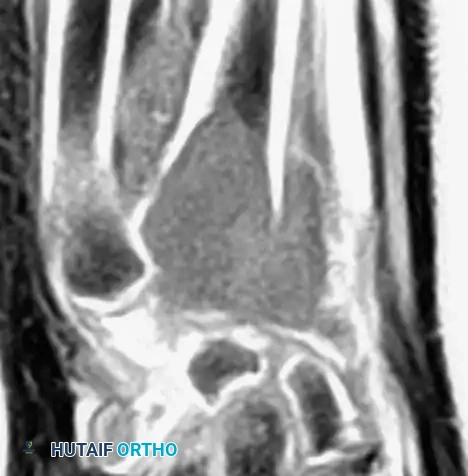

Advanced Imaging (MRI and CT)

Magnetic Resonance Imaging (MRI) is essential for evaluating the extent of the lesion, assessing articular cartilage integrity, and identifying secondary aneurysmal bone cysts (ABCs), which are present in up to 20% of patients. MRI typically reveals extensive bone marrow edema surrounding the lesion, which can be disproportionate to the tumor's size, further explaining the severe joint pain.